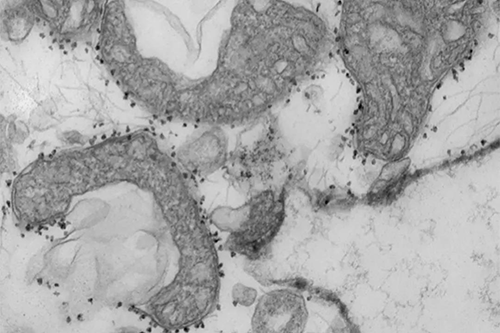

线粒体DNA水平是组织损伤的量度。图为从人肺释放的受损线粒体(深灰色区域)。线粒体周围的小黑点是磁性珠子,上面带有抗体,这些抗体用于隔离和研究已从垂死的组织中释放出来的不健康的线粒体。

(图片来源:Wandy Beatty)